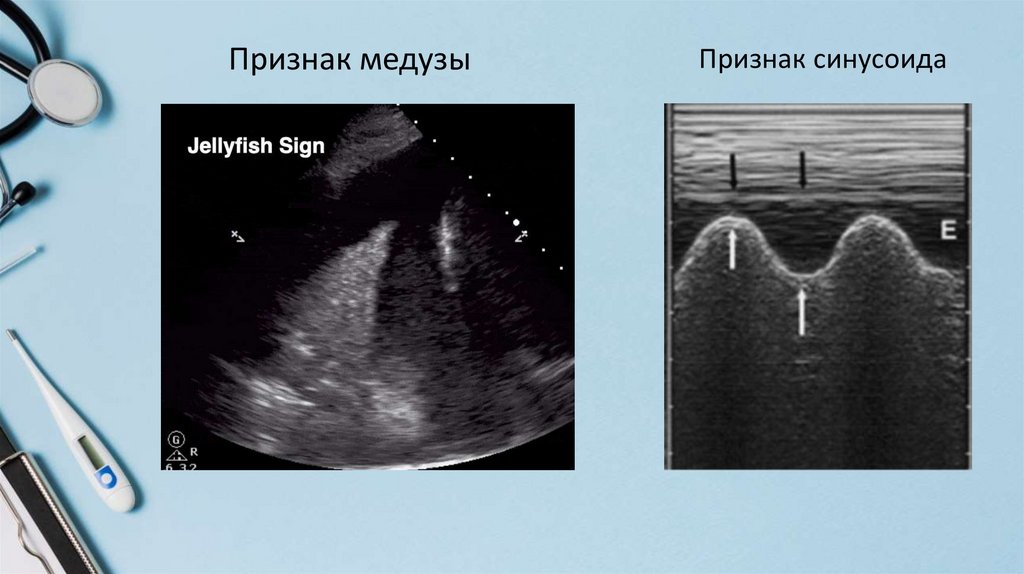

Признак медузы

Признак синусоида